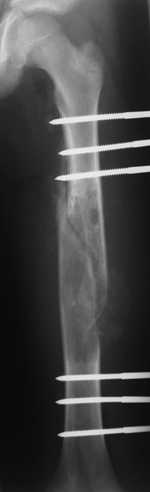

Re: Pathological fracture femur

послал Freih Odeh Abu hassan 23 Февраль 2008, 11:11

Most likely fibrous dysplasia, we had the same case but younger age patient 4 years ago treated by uniplanar ext fix followed by percut. curretage and bone marrow injection and healed well.

at this age IMN can solve the problem .